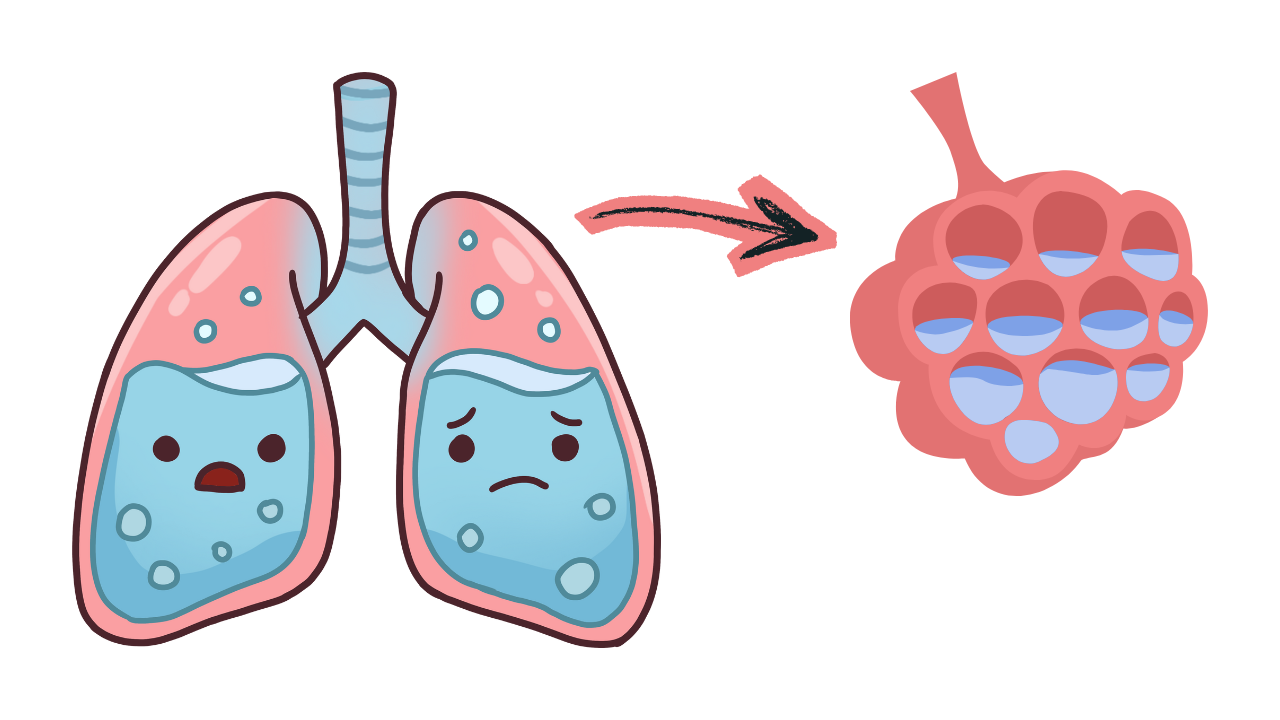

O Edema Agudo de Pulmão ocorre quando há acúmulo súbito de líquido nos alvéolos pulmonares, impedindo a troca gasosa adequada. Na prática, o paciente está se afogando no próprio líquido pulmonar. A causa mais comum é a falência aguda do ventrículo esquerdo, geralmente associada à insuficiência cardíaca, crise hipertensiva, infarto agudo do miocárdio ou sobrecarga volêmica.